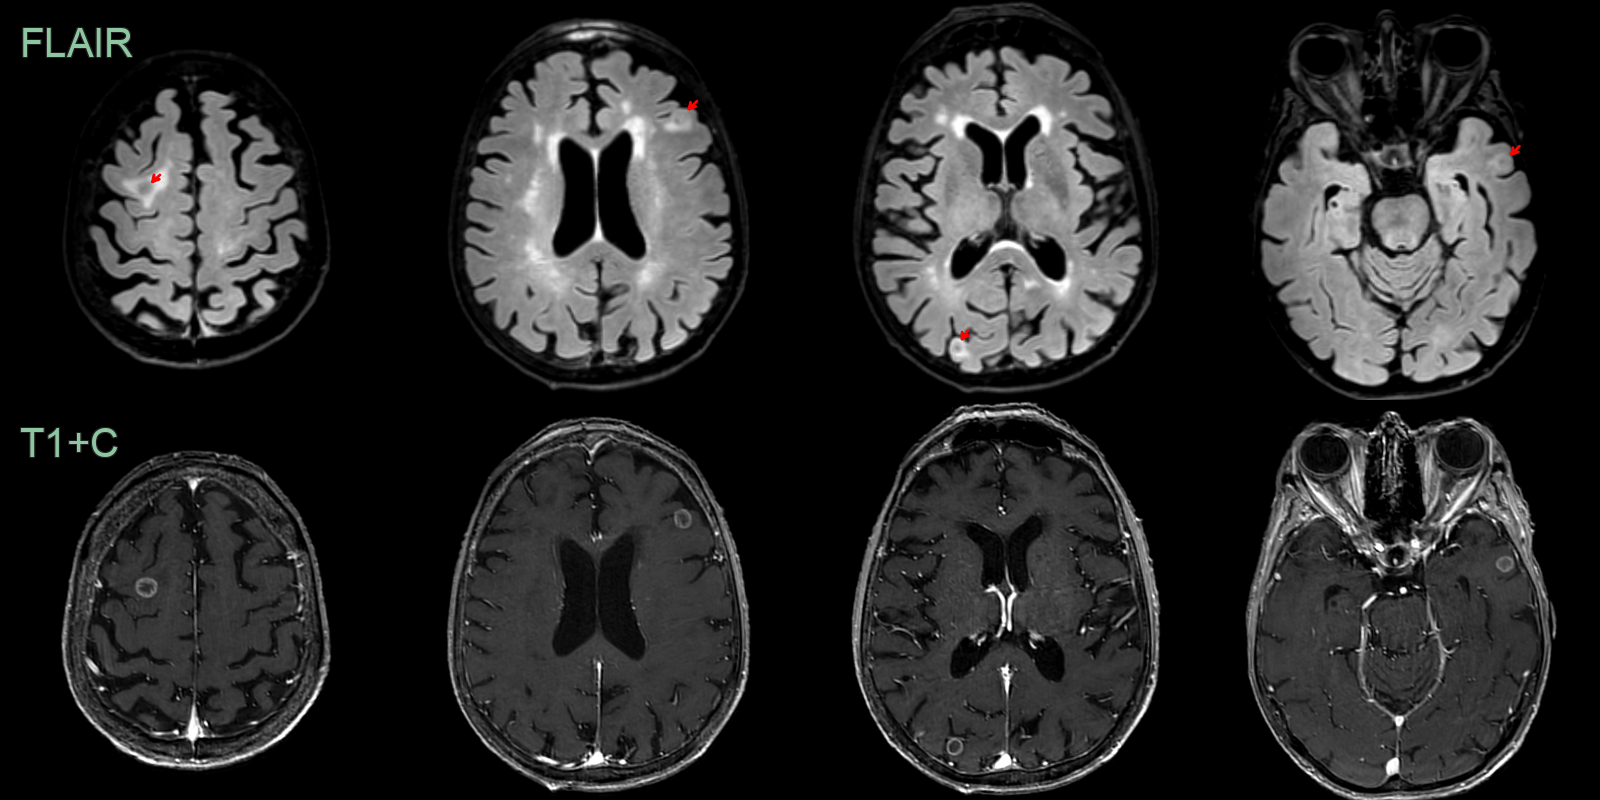

- A 70-year-old patient with small cell lung cancer presented with right leg weakness.

- MRI showed many peripherally enhancing lesions, the larges of which was in the left paracentral lobule.

- Following chemotherapy, MRI showed a marked reduction in the size of all of the lesions and the surrounding edema.